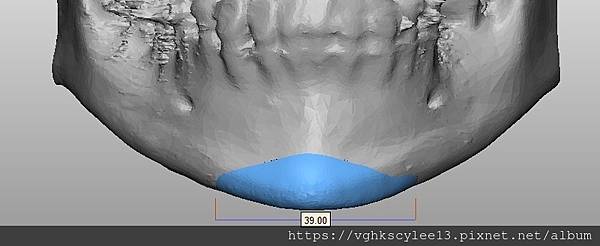

(下圖)3D模擬後工程師版的設計下巴假體的外型。

經過李醫師醫師對客戶外型的判斷,修改工程師的設計,建議更改後的假體模型(下圖)

(上圖)經過李醫師醫師對客戶外型的判斷,修改工程師的設計,建議更改後的假體模型。所以嘍,醫師的美感與專業度必須要做判斷,3D列印只是精準工具但是必須有專業醫師的判斷才可以完美!

下圖: 在李醫師確認後完美精準例印

窄小後縮的下巴,以精準3D列印技術來客製化醫師判斷後的外型下巴假體,一起改善嘴形相對的狀態。

窄小後縮的下巴,以精準3D列印技術來客製化醫師判斷後的外型下巴假體,一起改善嘴形相對的狀態。

3D模擬後 列印出吻合的設計下巴假體

下圖:或是以3D列印導板客製化下巴假體,以goretex材料按下巴導板來雕刻適合的形狀來訂製下巴,必要時把不規則的或不對稱骨頭磨平來改變術前傾斜。